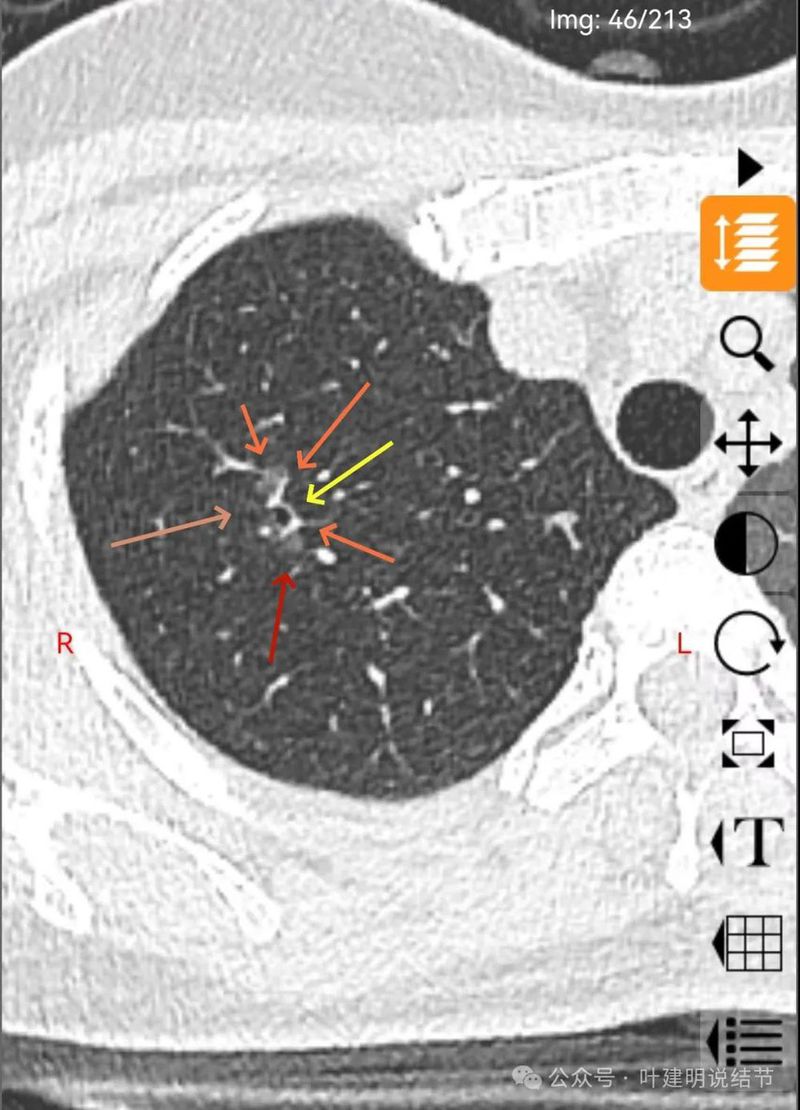

混合密度,月牙铲征,轮廓清,血管多支进入,灶内实性成分明显,表面不平分叶,灶内细支气管扩张。

分叶状明显,支气管扩张明显,血管弯征可见,整体轮廓清。

形态不规则、轮廓与边界清、多支血管进入穿行、支气管扩张,表面不平。

边缘处密度较淡。